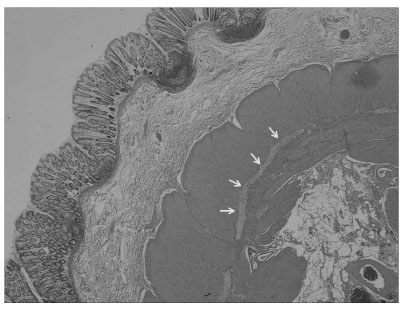

Fig. 3

Microscopic examination shows marked hypertrophy of the inner circular muscle layer and abnormal location of ganglion cells (oblique arrows) within the inner circular muscle layer (H & E, × 20).

Fig. 3 Microscopic examination shows marked hypertrophy of the inner circular muscle layer and abnormal location of ganglion cells (oblique arrows) within the inner circular muscle layer (H & E, × 20).